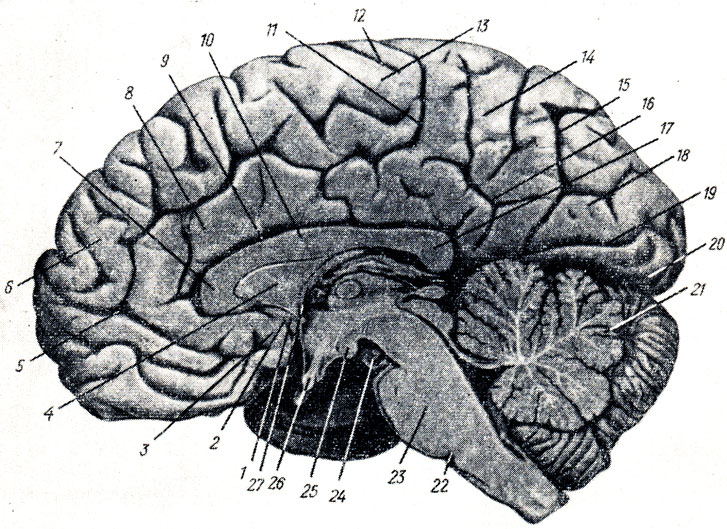

Анатомические снимки верхнелатеральной поверхности головного мозга